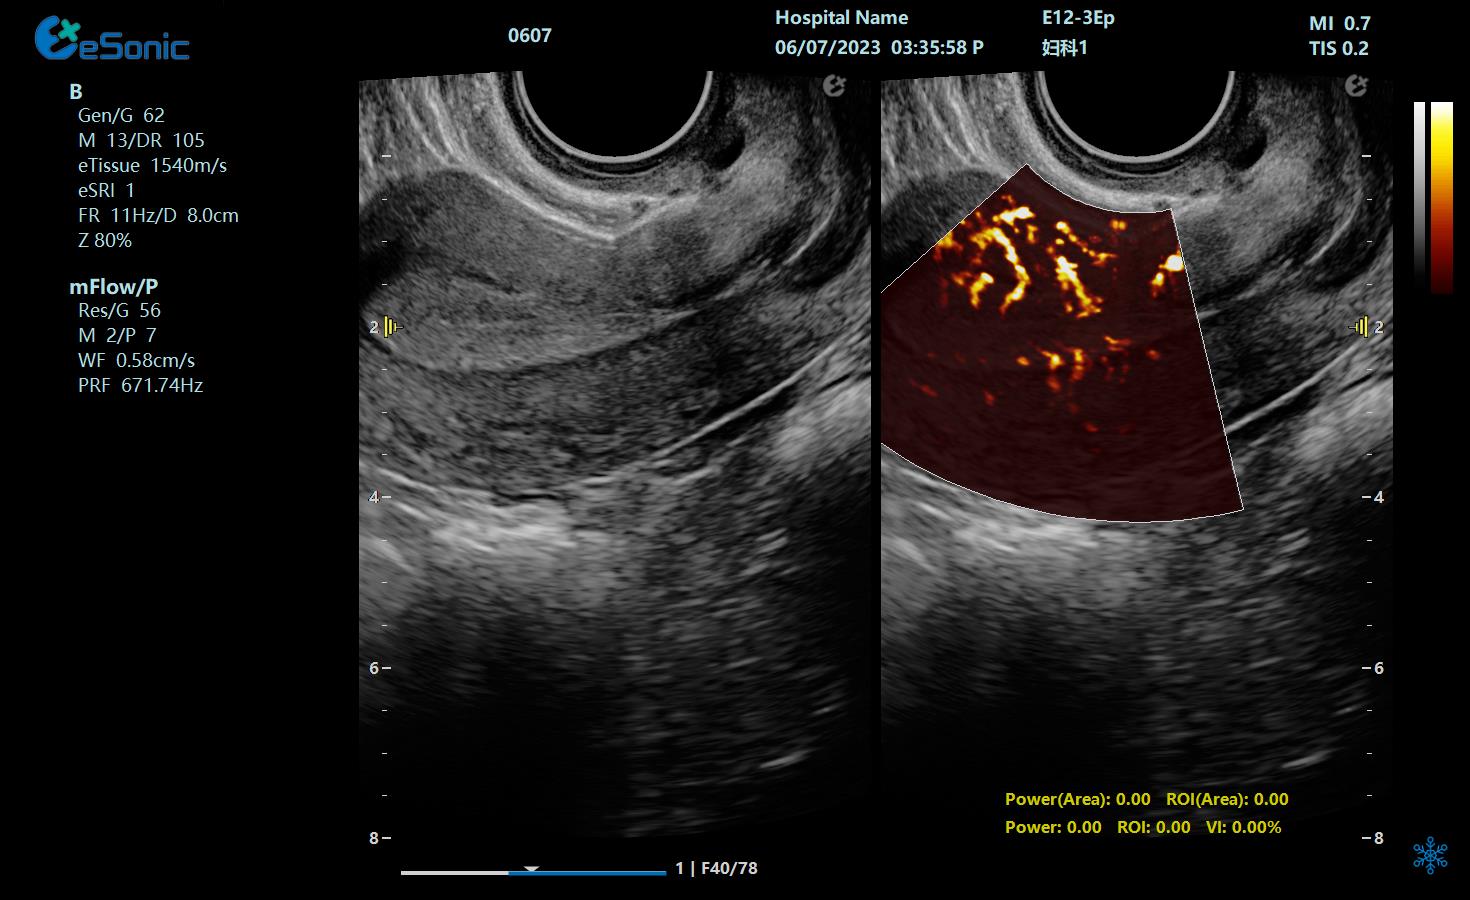

mFlow微血流显像技术,细节分辨率达100μm,支持频谱多普勒及VI血管指数定量。

mFlow子宫内膜下螺旋动脉